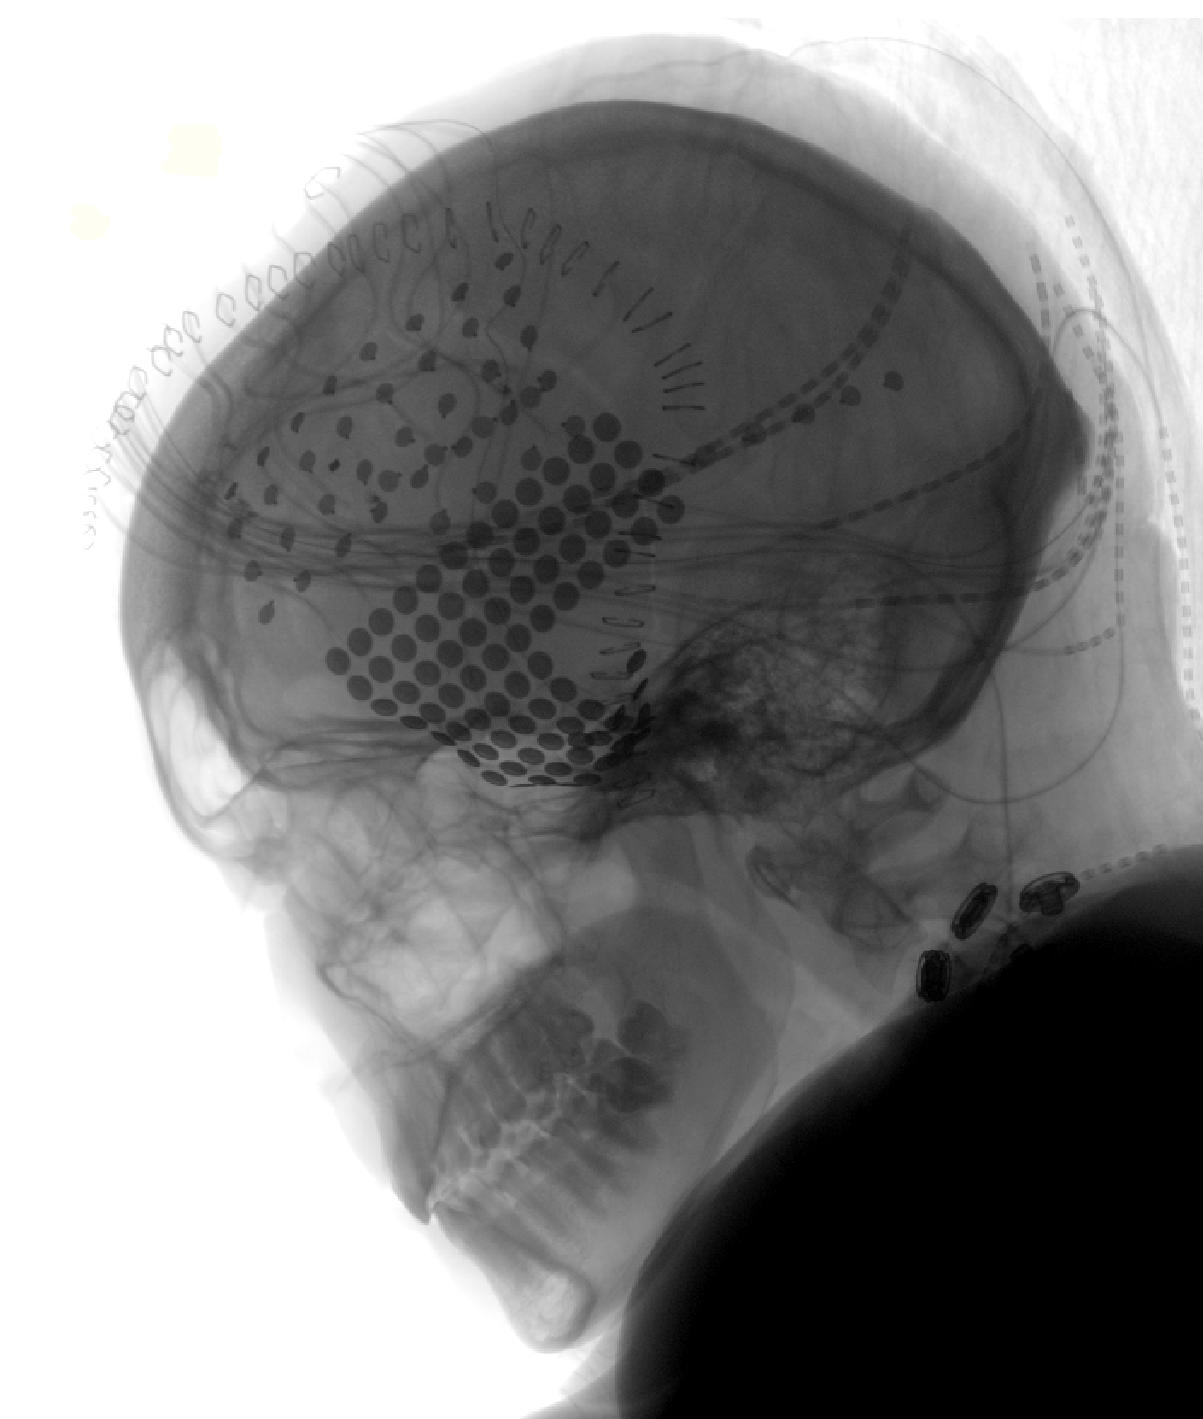

A head X-ray of one participant in the experiment shows the placement of electrodes over the frontal (top) and temporal (bottom) regions of the brain. These electrodes were placed on the surface of the brain to locate the origin points of epileptic seizures. While waiting for days in their hospital rooms, patients volunteered for other brain studies, including one attempting to pinpoint the brain regions that respond to music.